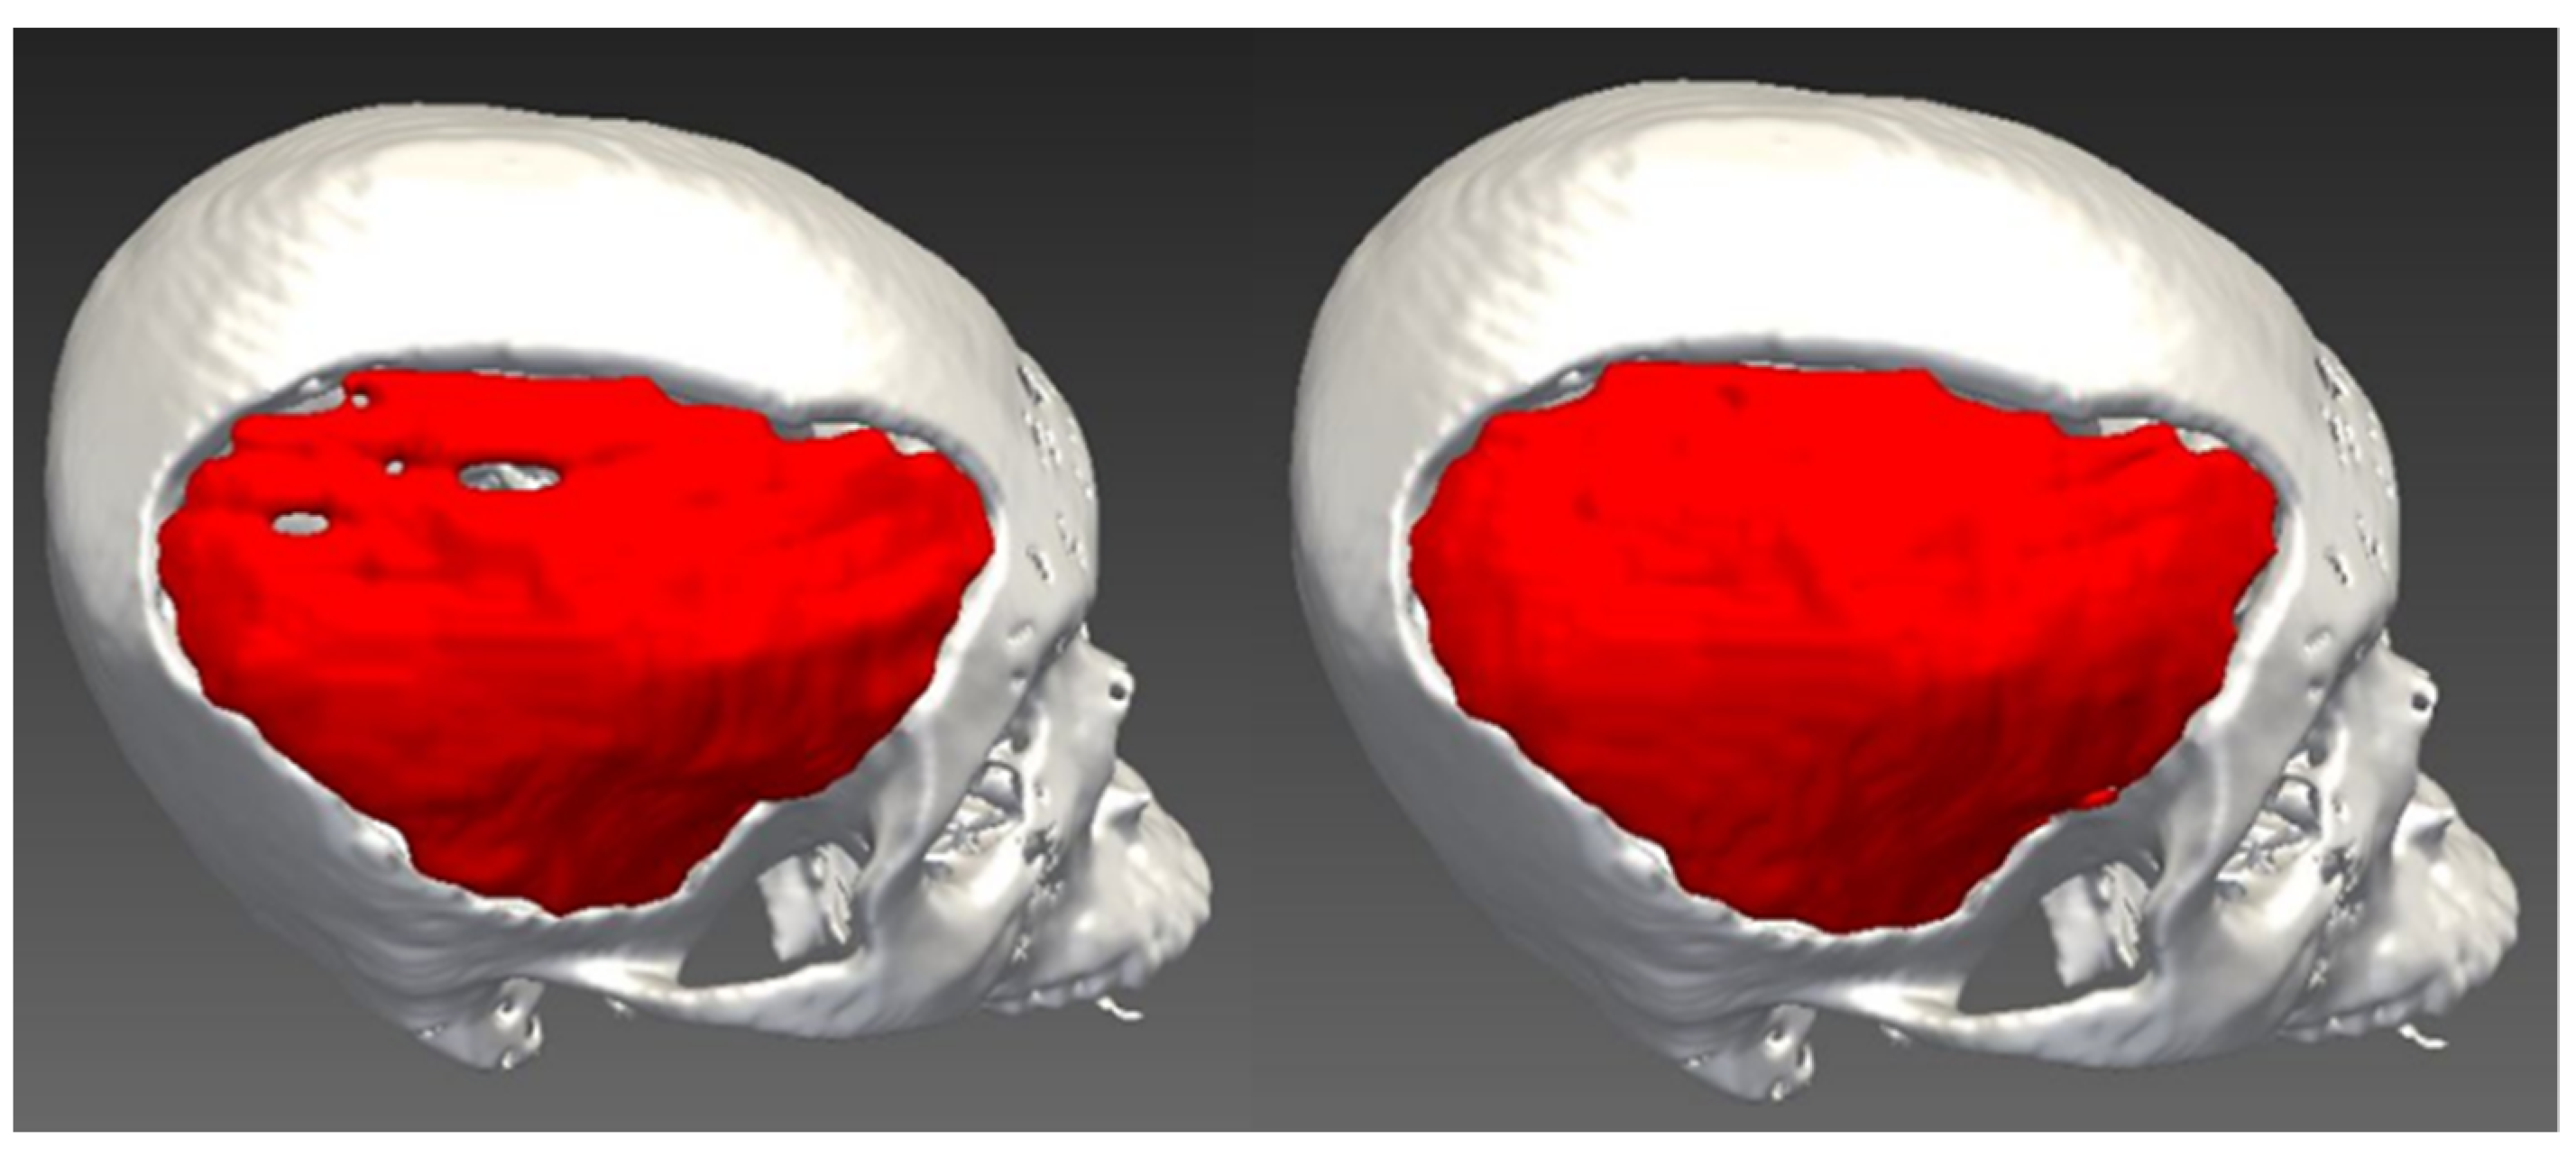

Once the line drawing of every tenth axial slice was performed, the 2D interpolation was executed applying the shape-based interpolation method, and the 3D cranial implant was successfully created, but not all surfaces of implants were reconstructed due to under-interpolation as shown in Figure 5.

Figure 5.

Green circles indicated unreconstructed surfaces due to under-interpolation.

As the selected axial slice was performed at every tenth slice, some areas were not interpolated; thus, holes could be seen on the implant. However, it can still be edited on the axial slice to cover the hole or defect of the interpolation, and the redo process can be carried out, as shown in Figure 6.

Figure 6.

The final cranial implant before editing (left) and after editing (right).

Alternatively, another method of selecting every fifth slice for interpolation was tested, as shown in Figure 7.